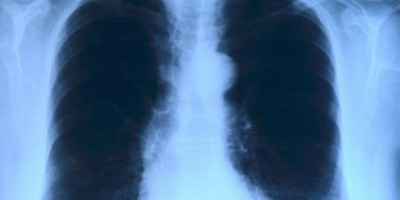

Sarajevski doktor Dragan Stevanović objavio je na Fejsbuku snimke pluća jednog od hospitalizovanih pacijenata koji je završio na kovid odeljenju

On je objasnio da se radi o mladom, do tada zdravom čoveku koji je nepušač, a čija su pluća vidno stradala usled infekcije korona virusom.

- Za one koji ne znaju, zdrav je crni deo pluća - objavio je dr Stevanović, dok se ne fotografiji vide velike bele fleke koje prekrivaju pkućna krila